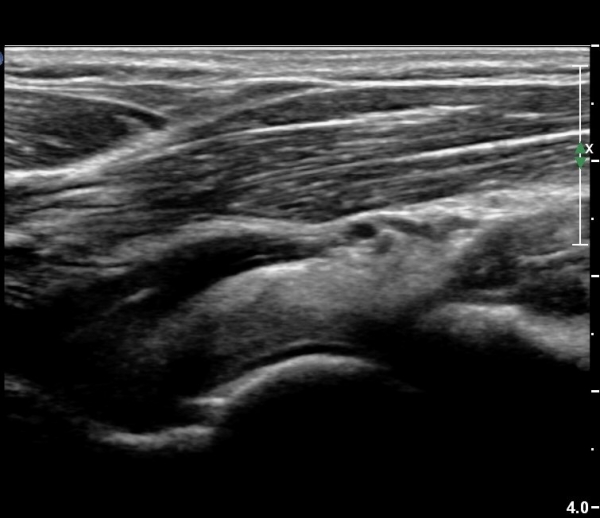

¼ÒµÎ Á¾´Ü¸é°Ë»ç¿¡¼­ ¼ÒµÎ¿Í ¿ä°ñµÎ Àü¹æ¿¡ ¼ö¾×Àú·ù°¡ °üÂûµÊ(»çÁø 3, 4).